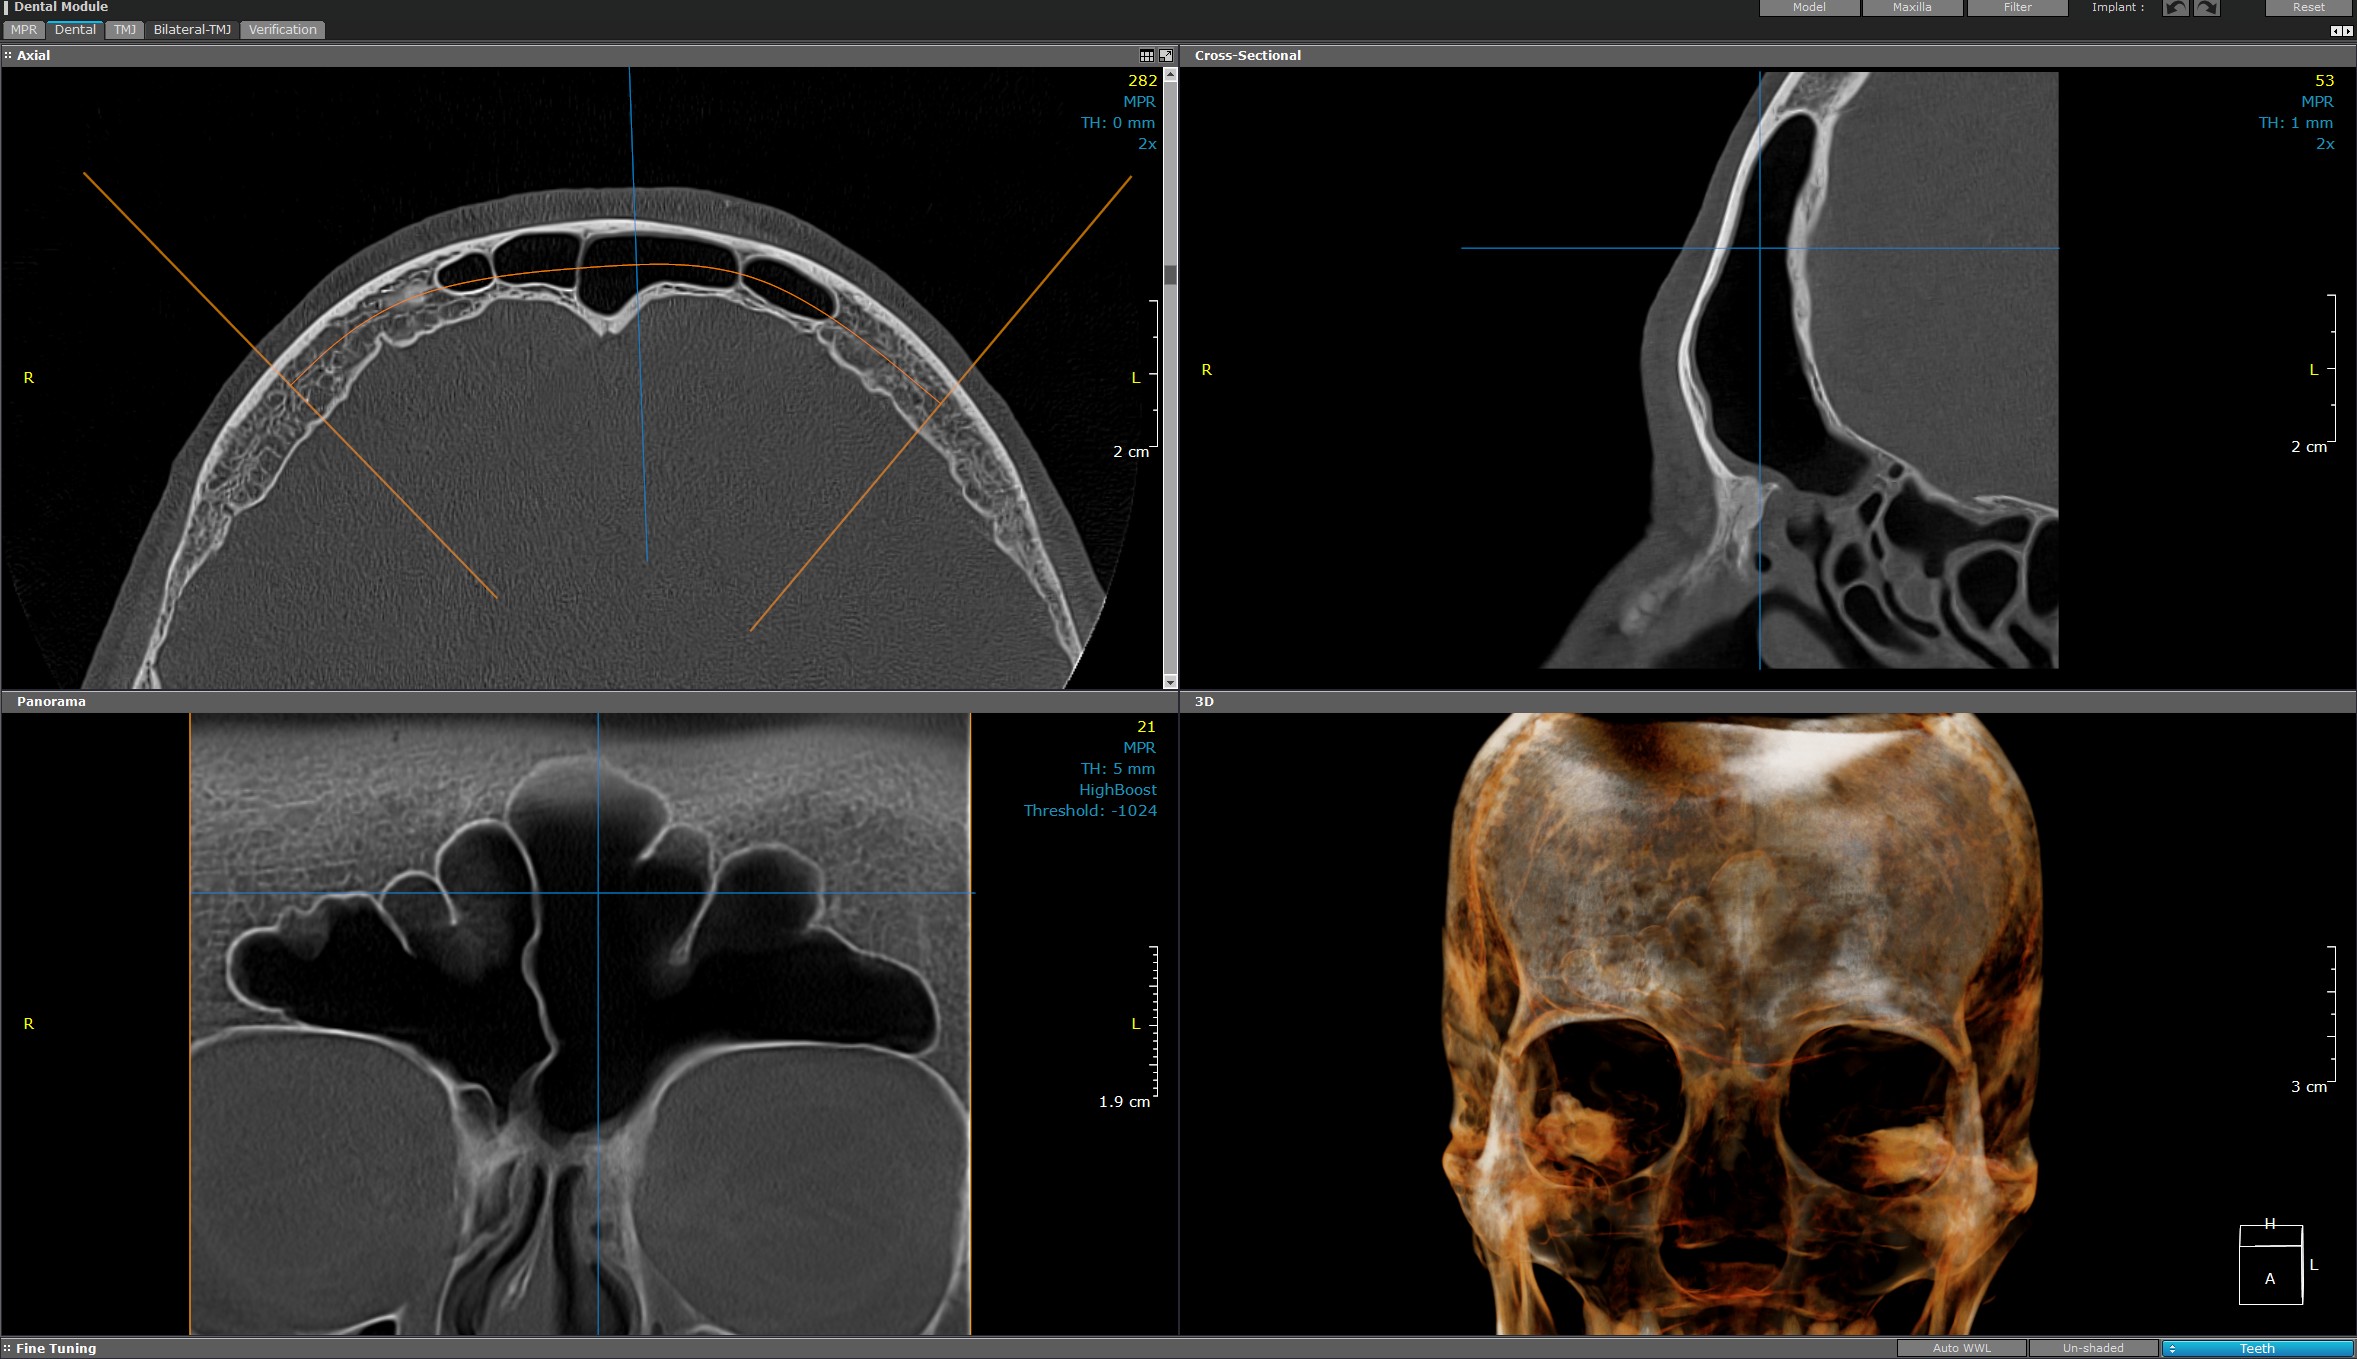

Computer tomograf (CT) de sinusuri ORL

Utilizează tehnologia avansată pentru a oferi imagini detaliate și precise, asigurând premisele evaluării și monitorizării afecțiunilor sinusale.

Folosind o tehnologie modernă, non-invazivă, această investigație oferă o vizualizare clară a structurilor sinusale maxilare, frontale și etmoidale, detectând inflamații, infecții sau alte disfuncții, patologii sau anomalii din domeniul ORL.

Rezoluția înaltă și capacitatea de scanare rapidă permit diagnosticarea precisă, ghidând tratamentele medicale necesare.